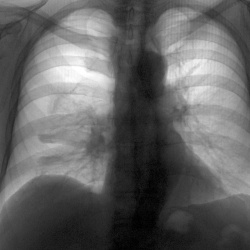

Добрый день. Рентгенограмма профилактическая. Возраст пациента 39 лет, жалоб не предъявляет. Первый снимок - сегодняшний, второй - от 2017 г. Не понравился левый лёгочный корень, но с учётом архива...